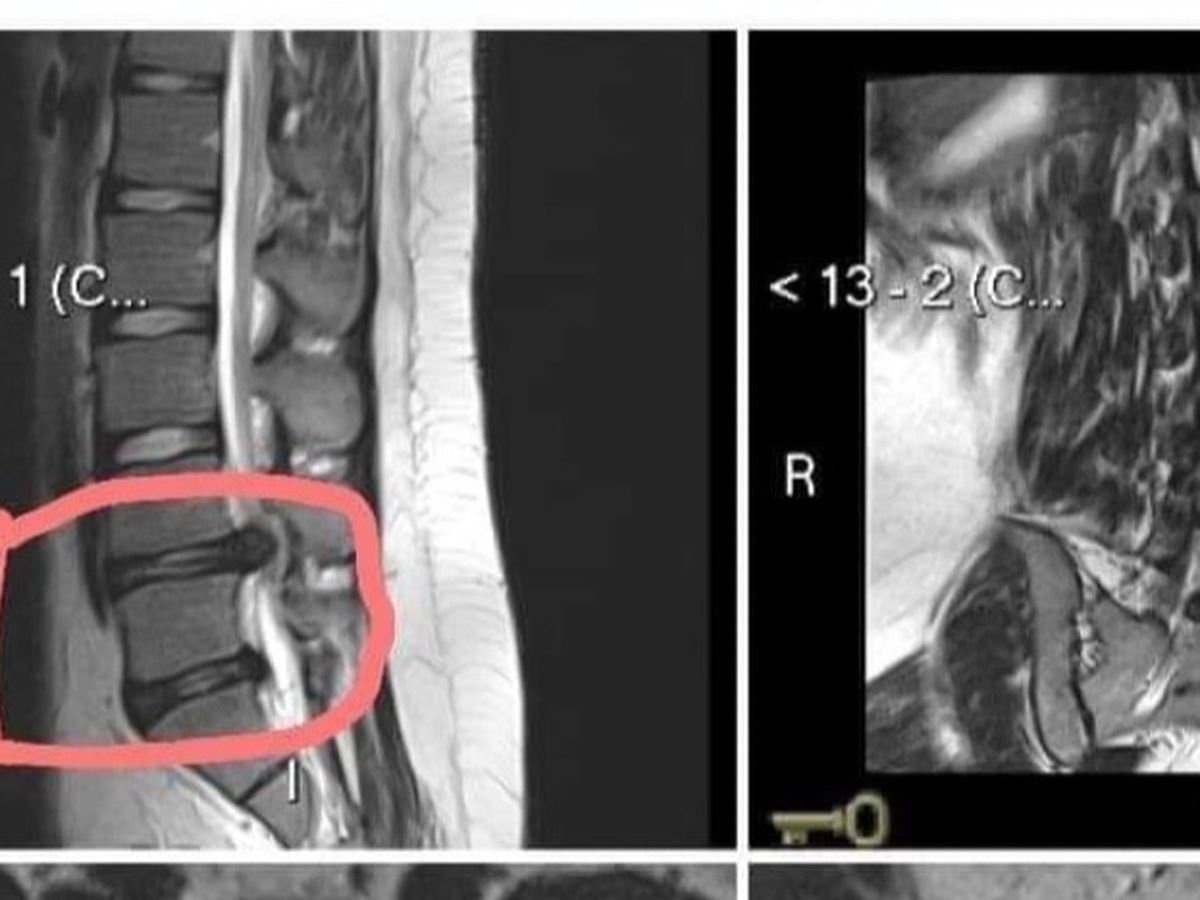

Ricardo is 16 years old. While taking a shower, he slipped and fell on the concrete so hard that he hurt his back. At first, he thought little of it and tried to recover at home. This happened about a month ago. In Mexico, getting medical intervention can get very expensive and it seemed easier to Ricardo to just try to get better with rest. Recently, his pain became more excruciating. His family thought that with more rest, he would get better, but when Ricardo suddenly was unable to move, his family was terrified. Ricardo's father took him to the hospital where the doctor diagnosed him with spinal injuries including subligamentous disc extrusion L4-L5, displacement of the nerve roots of the medullary sac, disc protrusion L5-S1, discopathy L4-L5 and L5-S1 Grade IV Pfirrman classification ( a total of 5 grades, thus, a very bad injury), and mild facet synovitis.